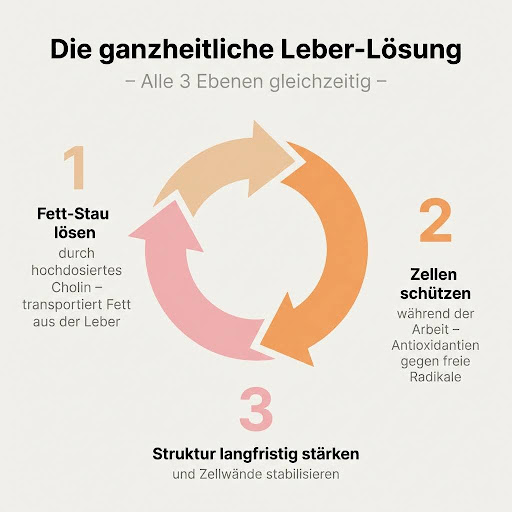

Mein Problem hat 3 Ebenen:

Ebene 1: Der Fett-Stau. Ohne Cholin konnte die Leber die Fette nicht abtransportieren.

Ebene 2: Oxidativer Stress. Während die Leber nämlich arbeitet, entstehen freie Radikale. Und ohne Schutz nehmen die Leberzellen Schaden.

Ebene 3: Ein “strukturelle” Schwäche. Was das bedeutet? Die Leber braucht stabile Zellstrukturen. Und ohne Unterstützung wird sie langfristig anfällig und “löchrig”.

Ich brauchte etwas, das:

- Den Fett-Stau löst (Cholin in hoher Dosis)

- Die Leber während der Arbeit schützt (Pflanzenextrakte)

- Die Struktur langfristig stärkt

„Das Wichtigste ist Ebene 1 – da muss der Fett-Stau gelöst werden. Deine Leber braucht Cholin, damit sie überhaupt Fette abtransportieren kann. Dazu kommt Inositol, das mit dem Cholin zusammenarbeitet und die Insulinsensitivität verbessert. Und dann noch Alpha-Liponsäure – das schützt die Leberzellen, während sie die ganze Arbeit machen. Das ist das Fundament. Ohne das läuft nichts.“

„Dann brauchst du Ebene 2 – die Pflanzenstoffe. Mariendistel mit richtig viel Silymarin, nicht diese Mini-Dosen aus der Drogerie. Die schützt die Leberzellen wie eine Rüstung. Artischocke sorgt dafür, dass genug Galle produziert wird für die Fettverdauung. Und Löwenzahn mit Wermut – das sind Bitterstoffe, die die ganze Verdauung ankurbeln. Diese Ebene schützt deine Leber, während sie auf Hochtouren läuft.“

„Und schließlich Ebene 3 – die Struktur. Da kommt Silizium ins Spiel, aus Bambus-Extrakt. Das stärkt die Zellstrukturen langfristig. Wie das Stahlgerüst in einem Gebäude – ohne stabiles Gerüst bricht irgendwann alles zusammen, egal wie gut der Rest ist.“